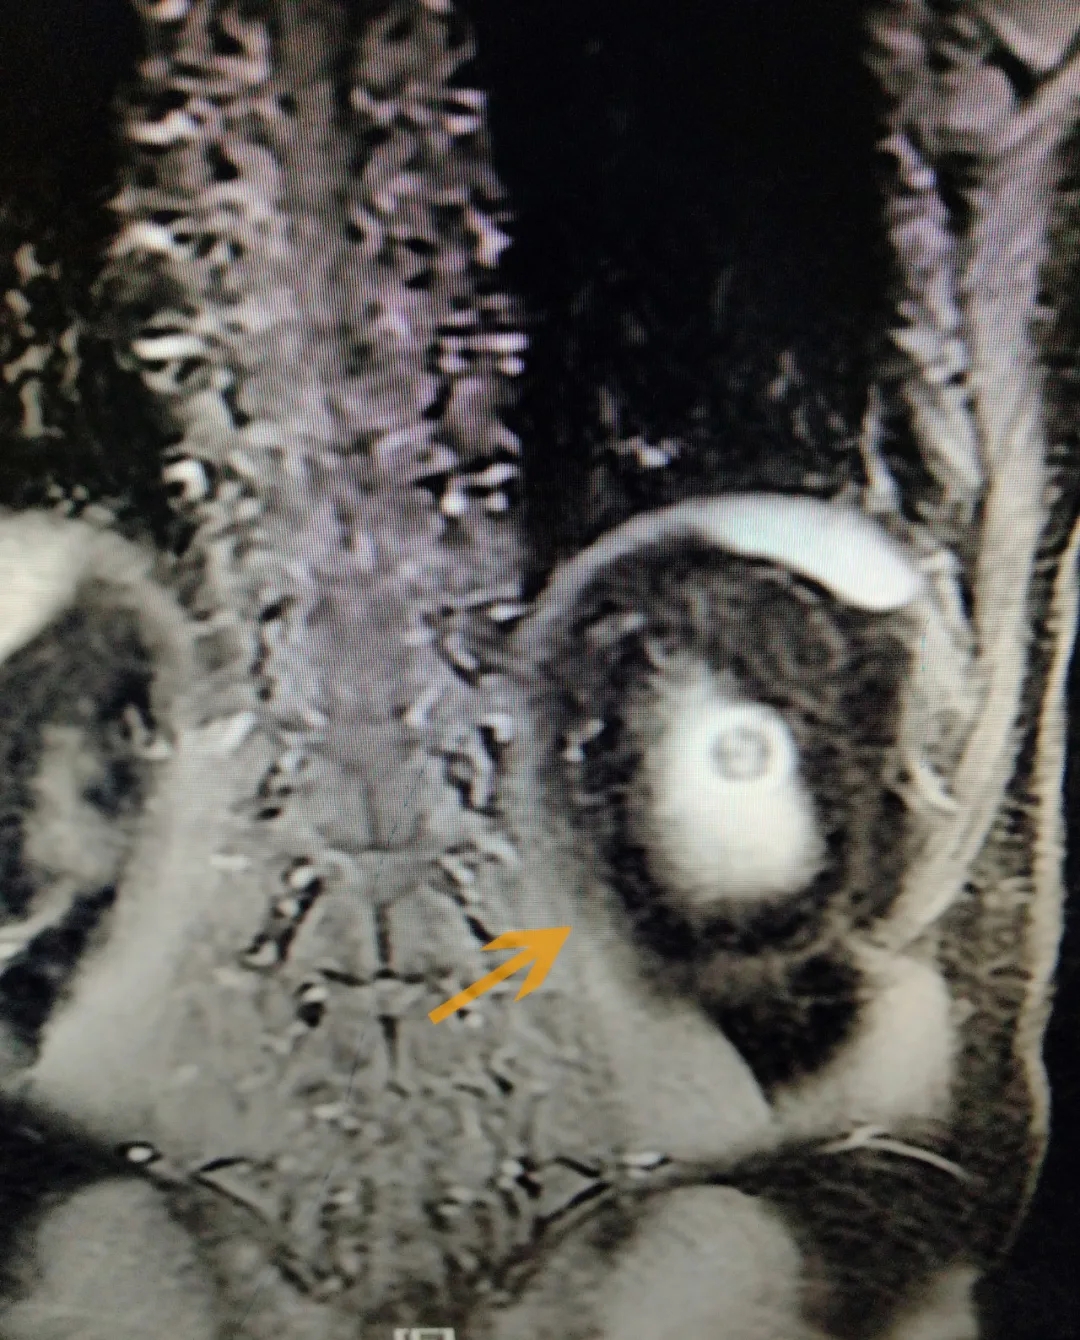

(导致黎先生腰部反复胀痛的左肾肿瘤)

4月2日上午,经过泌尿外科团队3小时努力,完整切除了黎先生的左肾肿瘤,手术顺利完成。术后,黎先生恢复较好,腰部也不再胀痛,精神状态好了许多,并于4月9日出院休养。